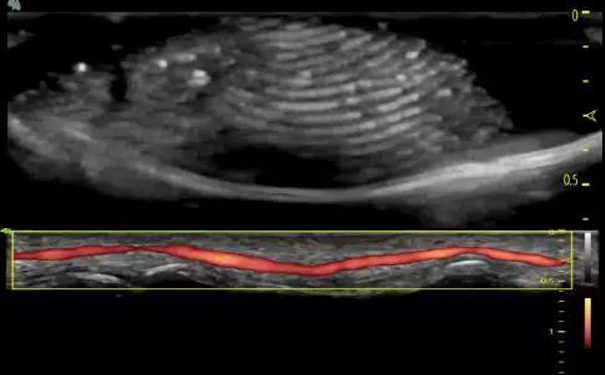

可以分辨0.1mm内中膜、极高的血流敏感度

飞依诺彩超颈动脉超声临床图